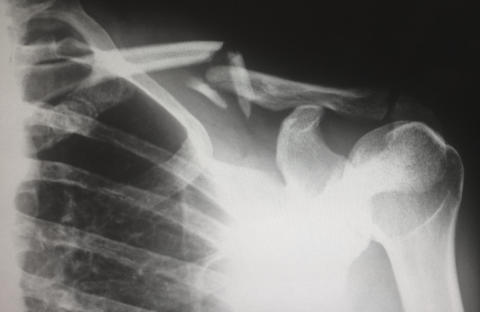

X-ray of a broken shoulder